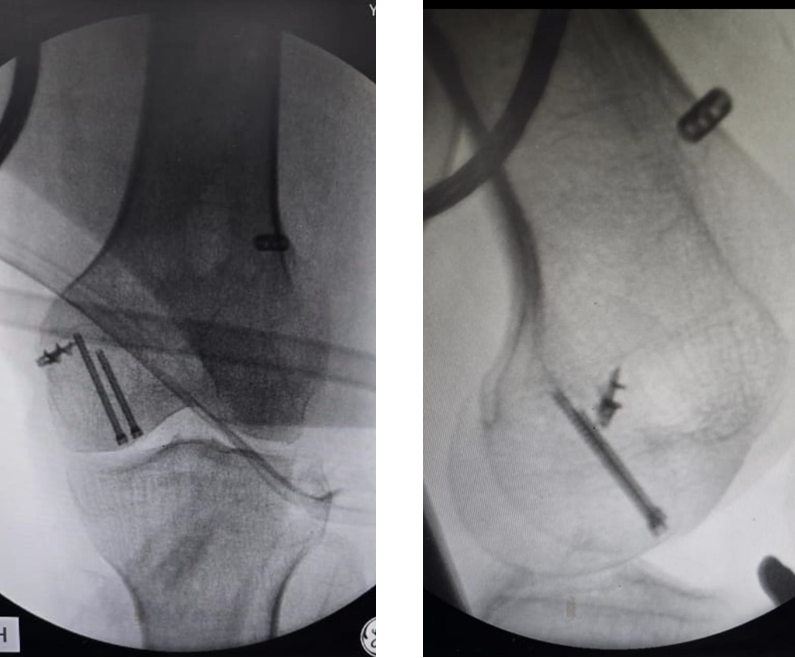

Radiographs (Fig. 1) and computed tomography scan (Fig. 2) of the knee revealed an undisplaced Hoffa fracture of the medial femoral condyle.

Figure 1: Pre-operative X-rays of the left knee showing an undisplaced medial femoral condyle Hoffa’s fracture.

The torn MCL was repaired using anchor sutures. Intraoperative C-arm images were taken (Fig. 6).

Figure 6: Intraoperative C-arm images.